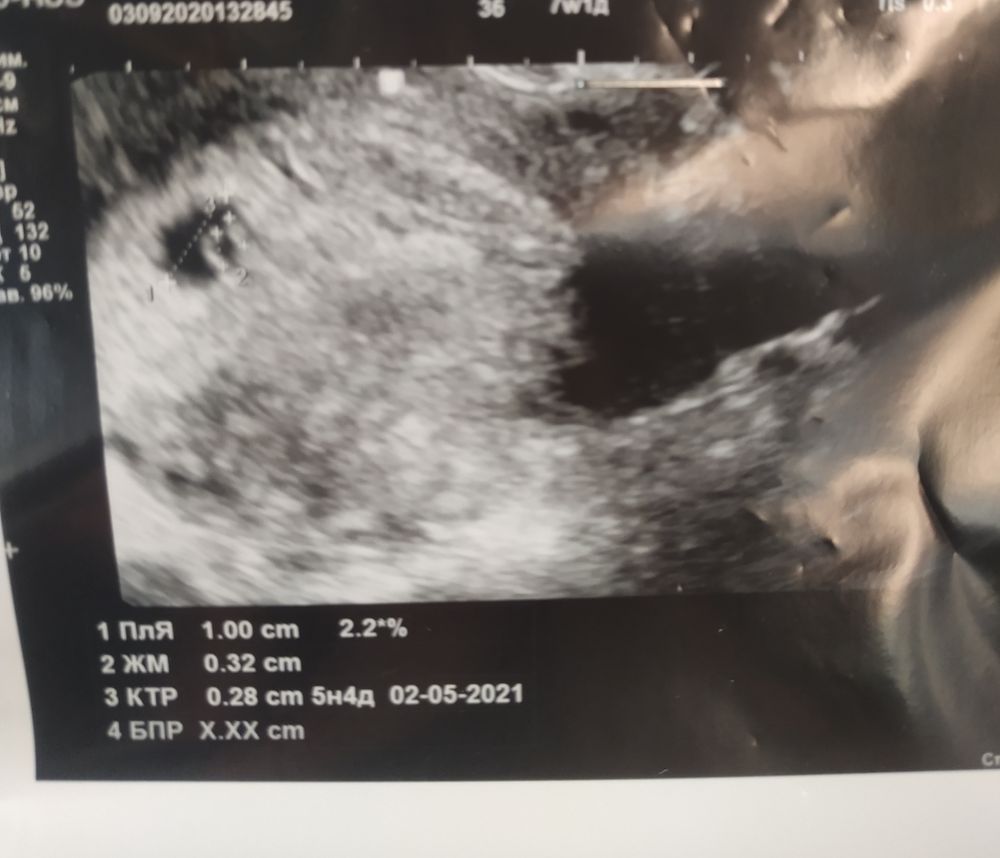

Наконец узи показало беременность!

Я уже писала раньше, цикл длинный, непонятный после визанны, сегодня 51 д. ц. , 12 дней назад только тест заполосатился я побежала на узи, и оно ничего не показало. Было велено прийти позже. Мы были в другом городе, эти 12 дней я места себе не находила, очень боялась вб, раз в матке ничего не было. Хоть девочки и писали тут что просто рано пошла. Хгч не сдавала. И вот сегодня приехали домой и я пошла к хорошему узисту. Есть пя и сердцебиение, срок поставили 5-6 недель. Что теперь. Я не понимаю это уже все, можно выдохнуть, если есть сердцебиение значит и эмбриончик есть? Я такая стала размазня, чуть что реву😭. Все равно боюсь очень зб, крайний раз на 12 недельке замер плод. Когда в жк идти? Или искать платного гинеколога, тыща вопросов, как в первый раз🙈